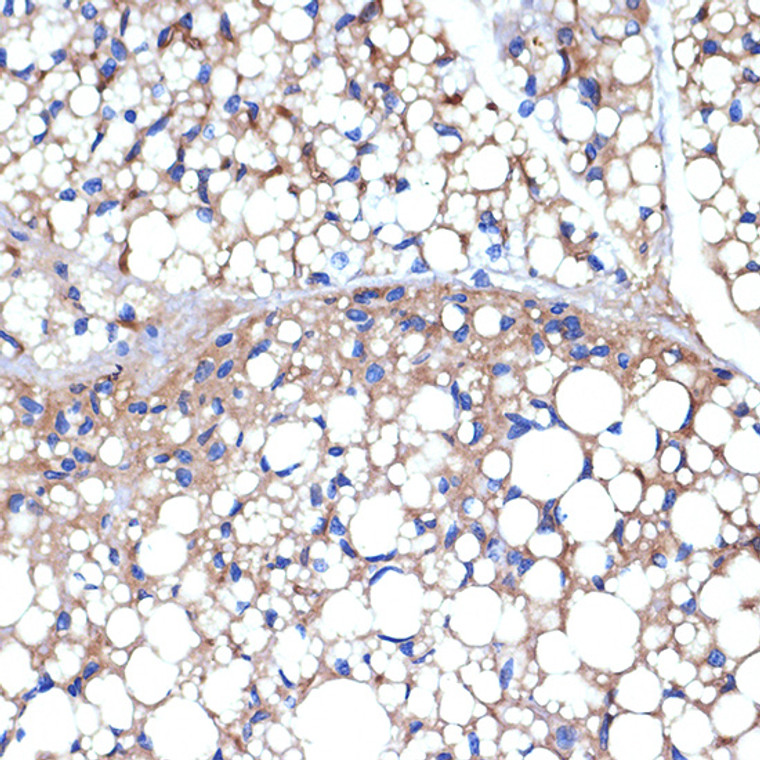

Rabbit monoclonal antibody anti-UCP1+UCP3 (1-307) is suitable for use in Western Blot, Immunohistochemistry and Immunofluorescence research applications. |

WB 1:500-1:2000IHC-P 1:50-1:200IF/ICC 1:50-1:200 |

Recombinant fusion protein containing a sequence corresponding to amino acids 1-307 of mouse UCP1+UCP3 (P12242). |